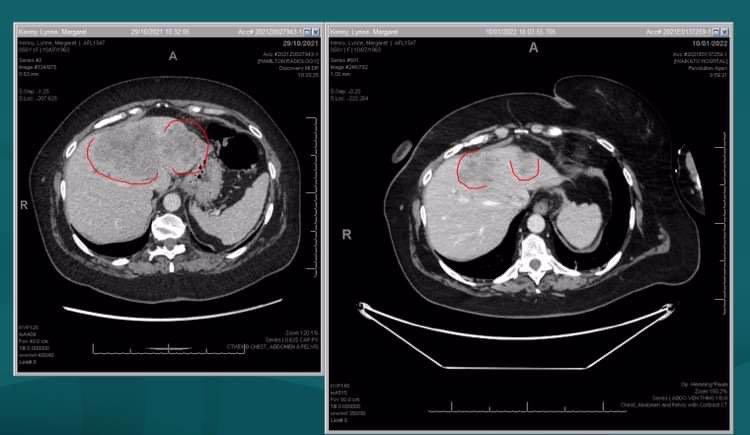

11 January 2022

Main image

Great news today with my scan results after 3 rounds of the unfunded drug Cetuximab there is significant shrinkage wahoo!! so I will definitely be carrying on with the treatment 😊

Thanks to those who have donated and helped me have the treatments so far I really appreciate it so much 😊❤️

It makes all the hard days with bad side effects well worth it

13 December 2021

I have had a scan since the last Update showing 3 of my liver tumours are stable but one unfortunately has had some growth My Oncologist said I needed to go onto the Unfunded drug Cetuximab in haste. I have now started the treatment in Tauranga fortnightly and with the cost of the treatment being $6290 each treatment plus Oncologist reviews at $253 fortnightly and the cost of travel I now need to extend my dates for my page to raise more funds for these costs and ongoing living costs I so appreciate each and everyone of you that have donated and shown your support for myself and my family I am truly so very grateful.